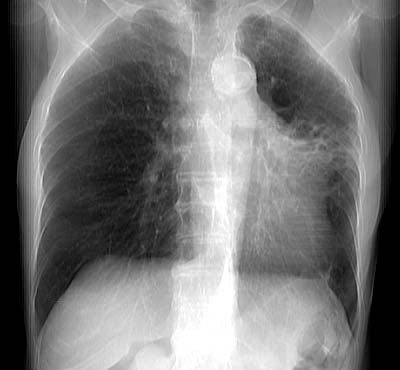

Re-projection image from volumetric data

Data acquired by R. Kato M.D., processed by K. Katada M.D.

Copyright (c) 1999 by Fujita Health University. All rights reserved.